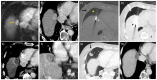

Percutaneous ablation is an accepted treatment modality for primary hepatocellular carcinoma (HCC) and liver metastases. The goal of curative ablation is to cause the necrosis of all tumour cells with an adequate margin, akin to surgical resection, while minimising local damage to non-target tissue. Aside from the ablative modality, the proceduralist must decide the most appropriate imaging modality for visualising the tumour and monitoring the ablation zone. The proceduralist may also employ protective measures to minimise injury to non-target organs. This review article discusses the important considerations an interventionalist needs to consider when performing the percutaneous ablation of liver tumours. It covers the different ablative modalities, image guidance, and protective techniques, with an emphasis on new and advanced ablative modalities and adjunctive techniques to optimise results and achieve satisfactory ablation margins.